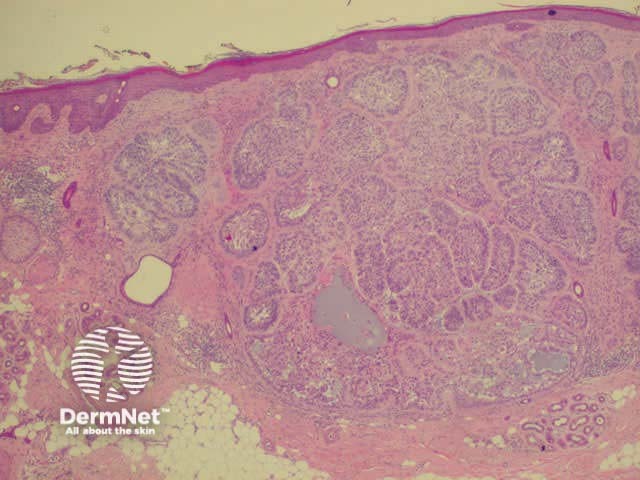

Histology of basal cell carcinoma